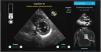

Caption AI© y Caption Guidance© son un nuevo software que permite a los intensivistas, incluso aquellos sin experiencia previa en ultrasonidos, la capacidad de realizar exámenes ecocardiográficos de manera rápida, precisa, y a pie de cama12–14. Esta nueva aplicación combina una información inmediata sobre la orientación e inclinación del transductor para optimizar la imagen y al mismo tiempo evalúa de manera automatizada la calidad de la misma, aumentando la capacidad de una interpretación inteligente (figs. 2 y 3)15,16.

Pantallas de 2 planos de un estudio realizado con la ayuda y guía de Caption AI© y Caption Guidance©. Se observa cómo hay diversos ítems de ayuda que hacen guiar el transductor hasta reconocer y conseguir un plano óptimo (que incluso clasifica su grado de optimización). De manera automática graba el mejor loop y proporciona las medidas que de él pueden obtenerse.

Caption AI© es el software que reconoce las estructuras a través de la inteligencia artificial y Caption Guidance© proporciona la orientación precisa del transductor a pie de cama durante el examen. Ambos softwares realizan una retroalimentación en tiempo real sobre la calidad de la imagen, para permitir una captura de gran calidad y de una manera automática17–19. Esta tecnología realiza un seguimiento continuo de las mejores imágenes vistas durante cada escaneo para que se capture automáticamente la imagen de mayor precisión de cada ventana, hay una revisión automática de los clips, los clasifica según la calidad de la imagen y selecciona los mejores para calcular parámetros básicos. El usuario tiene la libertad de explorar cada plano con la seguridad de que siempre podrá acceder al mejor clip de dos segundos de su examen con solo tocar un botón (vídeo 1, material adicional)20.